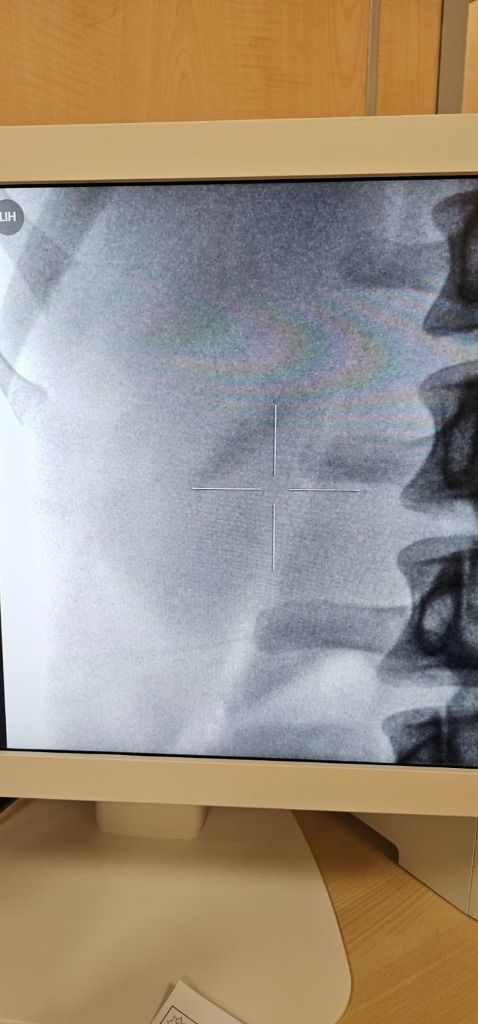

ESWL process under ultrasound control

Before

After

Before ESWL X-ray

After ESWL X-ray